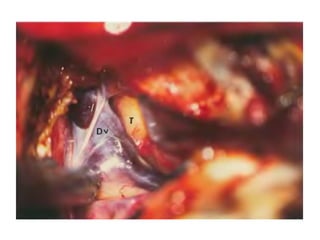

Right sided anterior petrosectomy on a cadaver dissection: intradural exposure

and operative field. PCA Petrous carotid artery; DPA drilled petrous apex; IPS

inferior petrosal sinus; BA basilar artery; VI 6th cranial nerve; AICA anterior inferior

cerebellar artery; P pons; V 5th cranial nerve

NOTE Inferior petrosal sinus at CLIVUS